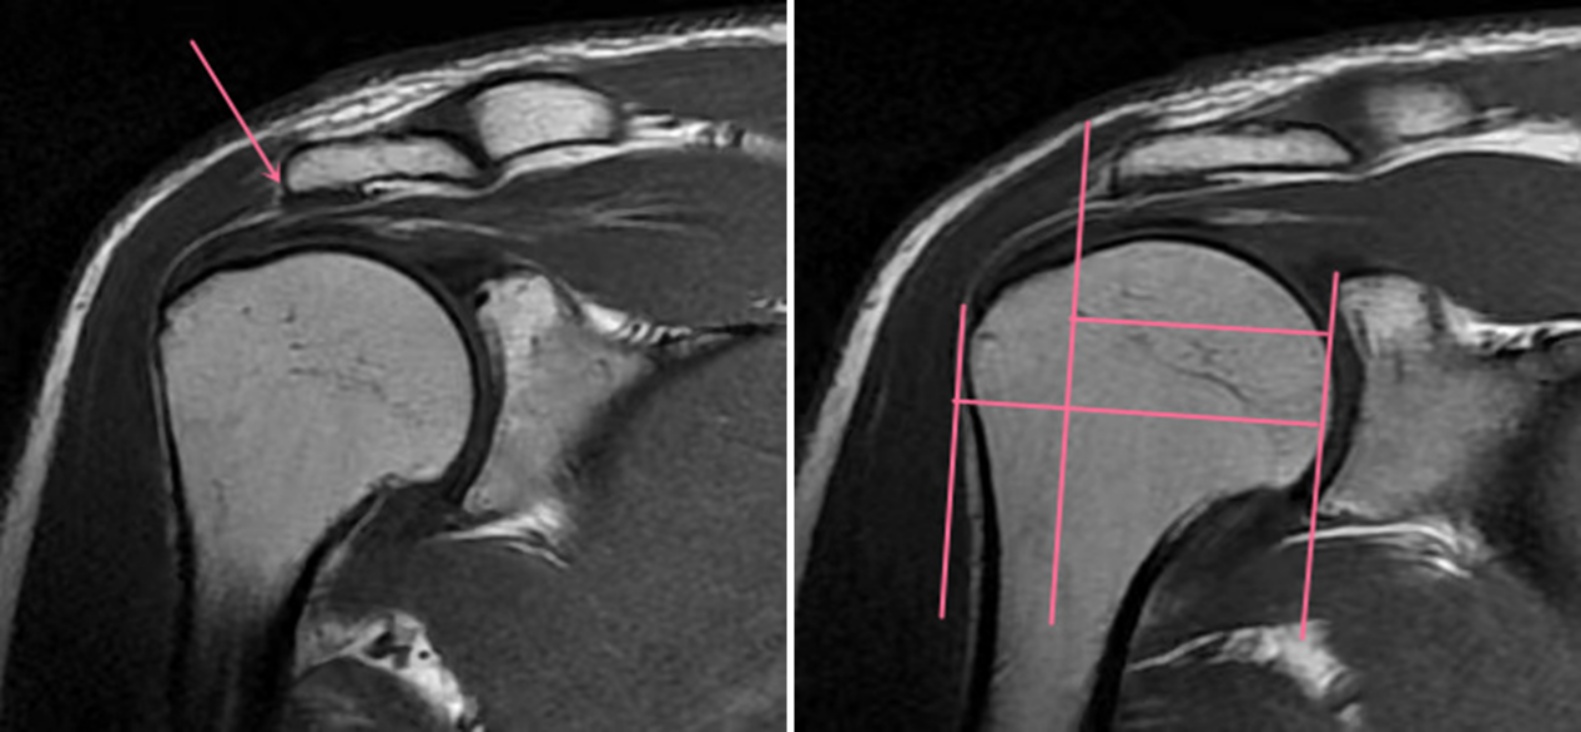

Figure 2. Illustrates the method for measuring the asymmetry index (AI) on MRI images

2. MRI图像测量AI方法

2) 参照Nyffeler等人[4]的研究,进行AI的测量(见图2):

在斜冠状位T1WI上,首先找到关节盂上下缘的最大截面,从上缘到下缘画一条直线,然后识别肩峰的最外侧点并用鼠标光标标记,然后通过肩峰最外侧缘作这条直线的平行线,同样方法用鼠标光标标记肱骨头最外侧点,然后通过肱骨头外侧缘作关节盂上下缘连线的平行线,肩胛盂缘到肩峰外侧缘的距离与肩胛盂缘到肱骨头外侧缘的距离的比值即为AI。

3) AHI的测量(见图3):

在斜冠状位T1WI上,测量肩峰下表面最下缘到肱骨头最上缘的最短距离即为AHI。

Figure 3. Depicts the method for measuring the asymmetry and hypertrophy index (AHI) on MRI images

3. MRI图像测量AHI方法